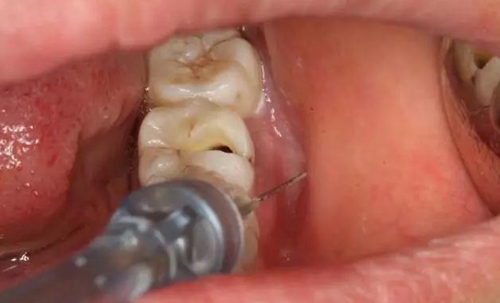

圖4.行下頜無痛阻滯麻醉。

4.jpg

圖5.加局部浸潤麻醉。

5.jpg